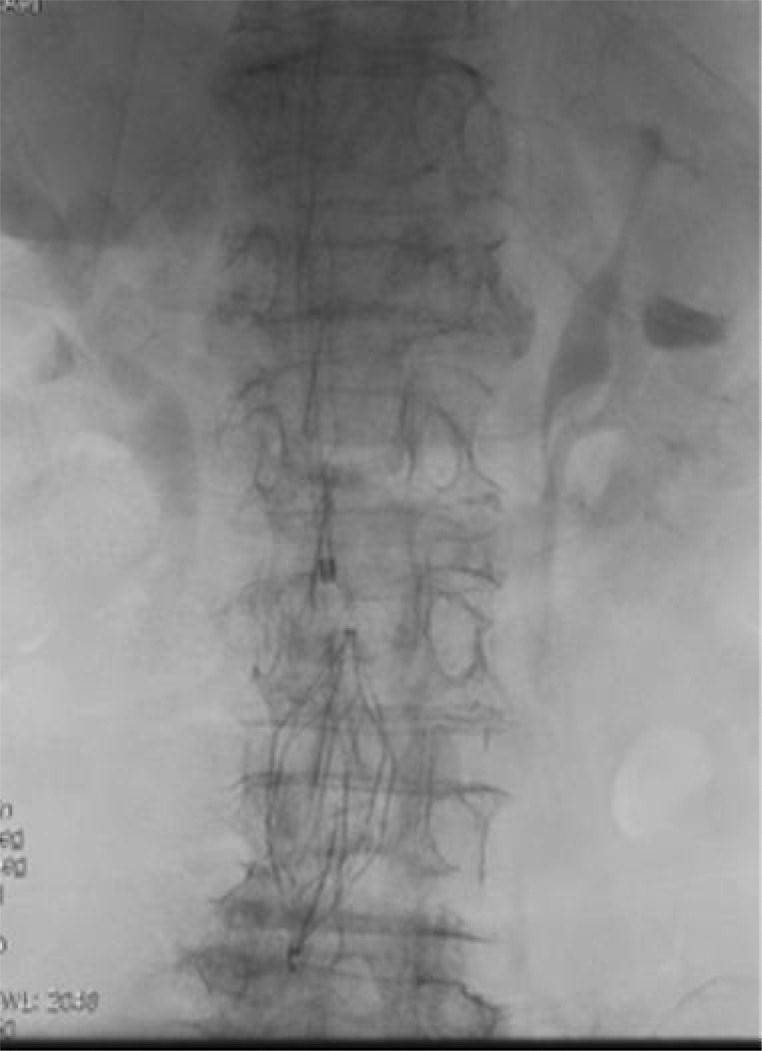

Case presentations: We had an equal number of males and females of the eight patients. Their ages ranged from 20 to 80 years. Five patients presented with bilateral lower limbs Deep vein thrombosis (DVT) of which one had a pulmonary embolism. Two other patients had extensive left femoral DVT and one had extensive IVC, iliac, femoral, and popliteal veins thrombosis. The medical records of seven patients, who had IVC filter placement in our department, were reviewed. The IVC filter was deployed with the aid of a C-arm fluoroscopic unit. In a single case, access was secured via an indwelling dialysis catheter.

Conclusions: All the patients had successful deployment with satisfactory postprocedure conditions. The intended benefit of pulmonary embolism prevention was achieved in the series of procedures that were performed. Indicating the value of IVC filter even in resource-poor settings and effort should be made towards exploring such intervention.